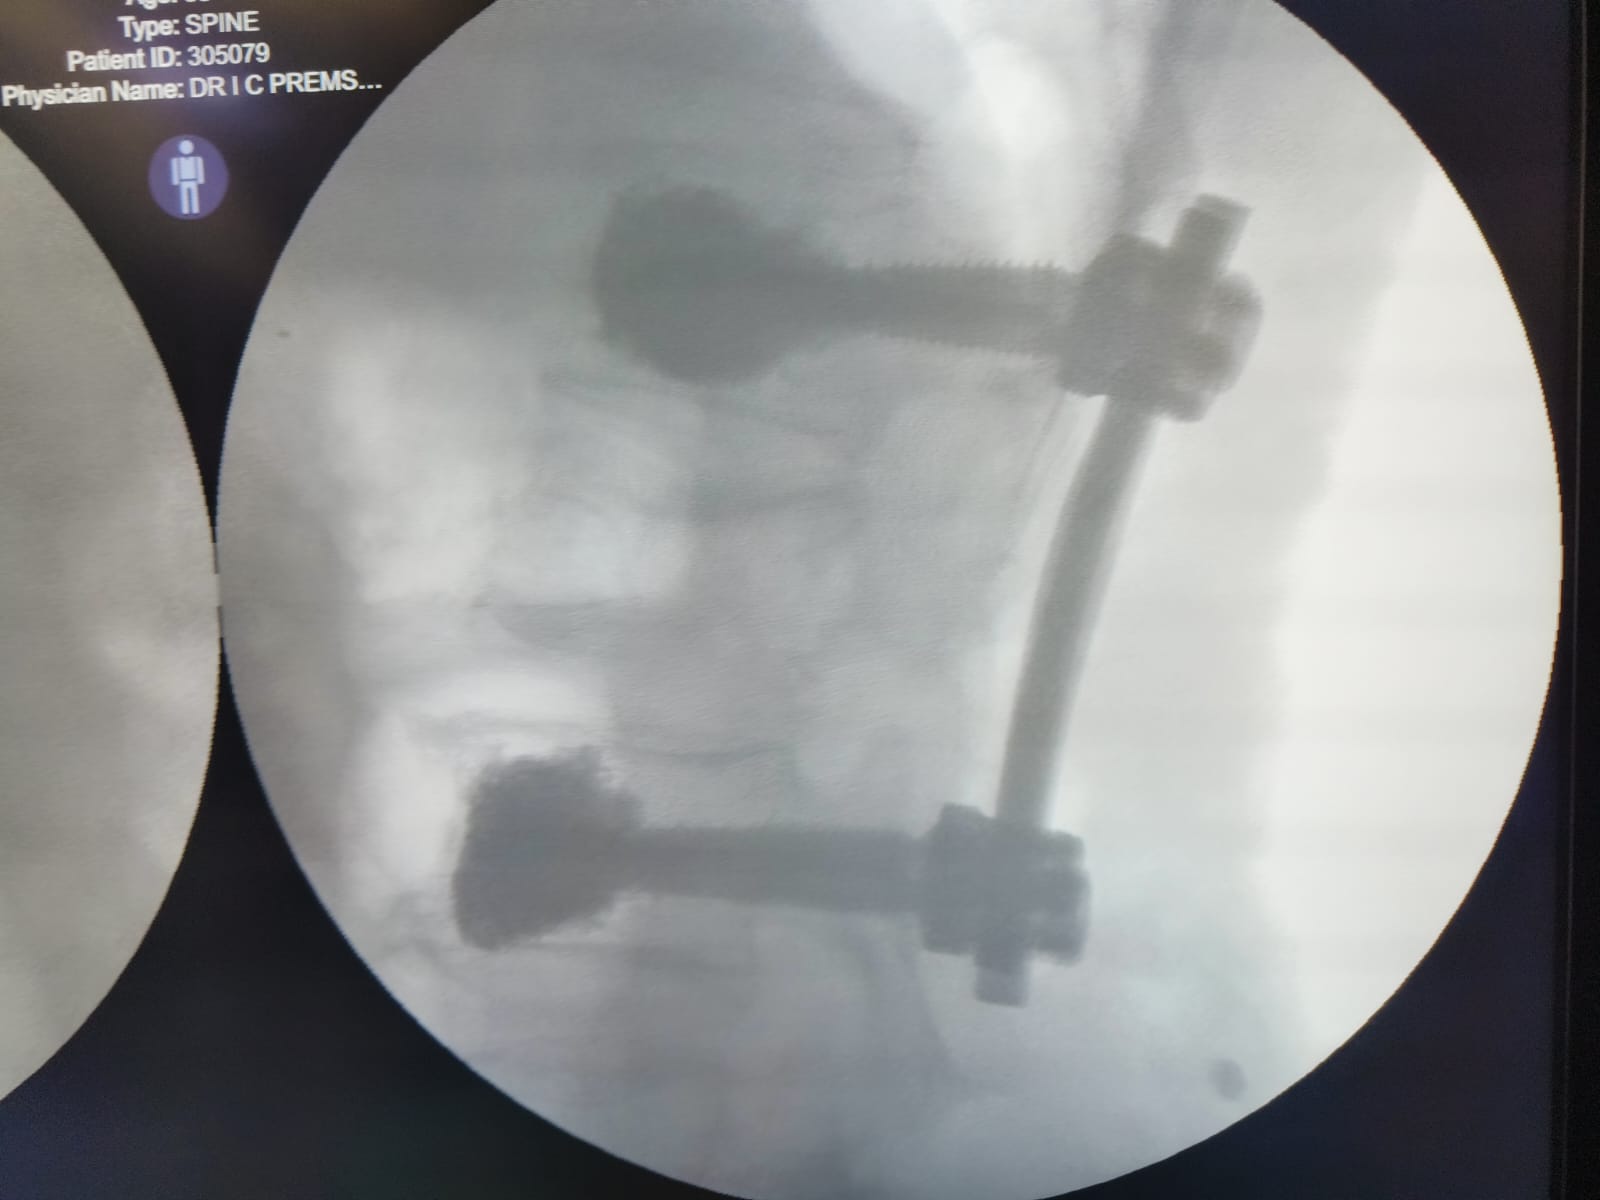

Neurovascular Surgery

Brain and Spinal Avm